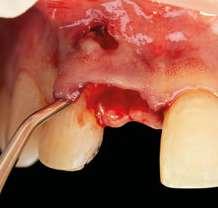

na paciente de 35 años (Figura 1) fue remitida a la Clínica de Odontología Reconstructiva de la Universidad de Zúrich debido a una infección crónica en el diente 11 y con expectativas estéticas muy altas. El diente 11 había sufrido un trauma hace 10 años y había sido tratado con multiple endodoncias sin éxito. El diente presentaba un absceso bucal (Figura 2), una bolsa periodontal aislado de 9 mm, y una ausencia de la tabla vestibular ósea (Figura 3). El diagnóstico se estableció como una fractura radicular vertical, lo que resultó en un pronóstico pobre. El plan de tratamiento consistió en una extracción combinada con preservación alveolar, colocación de implante diferido con injerto de tejido conectivo, una corona cerámica implantosoportada en 11 y una nueva carilla de cerámica para el diente 21.

El diente 11 fue extraído (Figura 4), seguido por la preservación alveolar. Se realizó un injerto pediculado de espesor parcial rotado del paladar (Figura 5), junto con una membrana de colágeno reabsorbible, un xeno-injerto bovino y cianoacrilato sellando al alveolo (Figura 6). La provisionalización consistió en un puente adhesivo de resina con dos alas de metal. El alveolo se dejó cicatrizar durante 6 meses, después de los cuales se tomó una impresión digital así como un escáner CBCT (Figura 7). Se llevó

a cabo una planificación digital para una cirugía guiada de implante en una posición protéticamente ideal (Figura 8). El implante 11 se colocó completamente guiado a través de una férula (Figura 9). Las dimensiones del reborde alveolar eran ideales para la colocación del implante en una posición atornillada (Figura 10), al igual que la calidad del hueso cicatrizado. Un injerto de tejido conectivo subepitelial fue estabilizado ocluso-bucalmente al implante (Figura 11) y el puente adhesivo fue recementado (Figura 12). Después de 3 meses de cicatrización, se realizó una restauración provisional y se acondicionó adecuadamente para dar forma al perfil de emergencia, imitando el del diente adyacente (Figura 13). Después de una fase provisional, se tomó una impresión analógica individualizada para el implante 11 y el diente 21 (Figura 14). El laboratorio fabricó una corona implantosoportada de zirconio con cerámica estratificada para el 11 y una carilla laminada feldespática para el diente 21 (Figura 15). Ambas restauraciones fueron colocadas en la paciente y mantenidas. La paciente quedó muy satisfecha con el resultado estético de las restauraciones (Figuras 16, 17). Después de 2 años, el implante permanece saludable con el hueso marginal estable (Figura 18) y una buena calidad y cantidad de tejido blando.